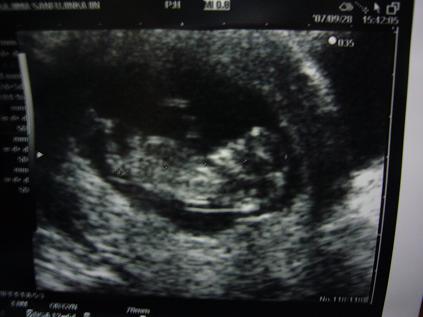

今日は病院へ行ってきました

精密検査で、異常がないか調べる日でした

まったく異常なしでした

ほっと安心

そして、ちゃんと人の形になってる!と

最初は豆粒みたいだったんですよねぇ

なんか花の時もだけど、こうなると感動しますねぇ

それも

ああ、動いてるっ!って

そんなに激しくじゃないけどぴょこんぴょこんってちょっとピクンってなるじゃないですか

あれが嬉しくってたまりませんでした

そこでわかった新事実・・・・・

ええ・・・・出産予定日が確実に決まったんですが

4月5日が4月17日になりました・・・・・

なんですか・・・このズレは

1日~5日ぐらいのズレは勘弁しましょう

でも12日もズレるっていったい・・・・・

まあこれで確実に4月の子になりました

花の時みたいに14日ずれても4月の3日・・・・

ですよねぇ(汗

まあ、元気に産まれて来ればよしとしますか

後は性別だけ!

男か女か・・・・わかるのは当分後だそうです